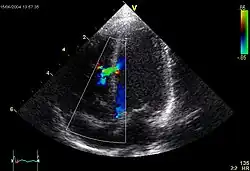

Ventricular septal defect (VSD)

Makro: Loch im Kammerseptum, meist im membranösen Teil.

Folge: Links-rechts-Shunt